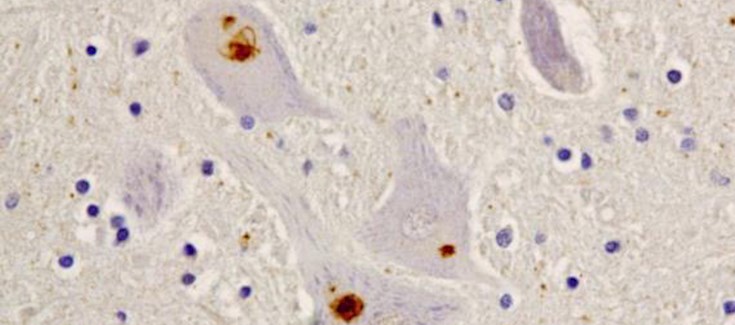

El gen CCNF (también llamado FBX01) codifica la ciclina F, una proteína de la familia de las ciclinas. La ciclina F participa en la formación del complejo E3 ubiquitina – proteína ligasa, que a su vez forma parte del sistema ubiquitina proteasoma (SUP). La integridad de las funciones celulares depende del mantenimiento o integridad (homeostasis) de las proteínas (proteostasis), lo que implica la eliminación de las proteínas mal plegadas a través del SUP y del sistema autofágico – lisosomal (por el descubrimiento de este ultimo sistema se le concedió el premio Nobel de Medicina y Fisiología de 2016 a su descubridor, Yoshinori Ohsumi). En un modelo celular, los investigadores demostraron que las variantes de ciclina F asociadas a ELA/DFT daban lugar a la acumulación de proteínas ubiquitinadas (unidas a ubiquitina) y a la disfunción del SUP. También observaron un aumento de proteína TDP-43 ubiquitinada (un marcador molecular de la mayoria de los casos de ELA/DFT) en neuronas portadoras de la mutación de CCNF.

Uno de los casos estudiados con la nueva mutación corresponde a una paciente de ELA que donó su tejido cerebral y la médula espinal al Banco de Tejidos CIEN. En el estudio también participaron investigadores del Hospital Gregorio Marañón y Doce de Octubre, de Madrid, y del Centro de Investigación Biomédica en Red de Enfermedades Raras (CIBERER), del Instituto de Salud Carlos III.